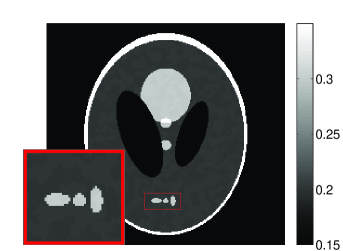

• [63] C. W. Dodge, A rapid method for the simulation of filtered X-ray spectra in diagnostic imaging systems (ProQuest, 2008).